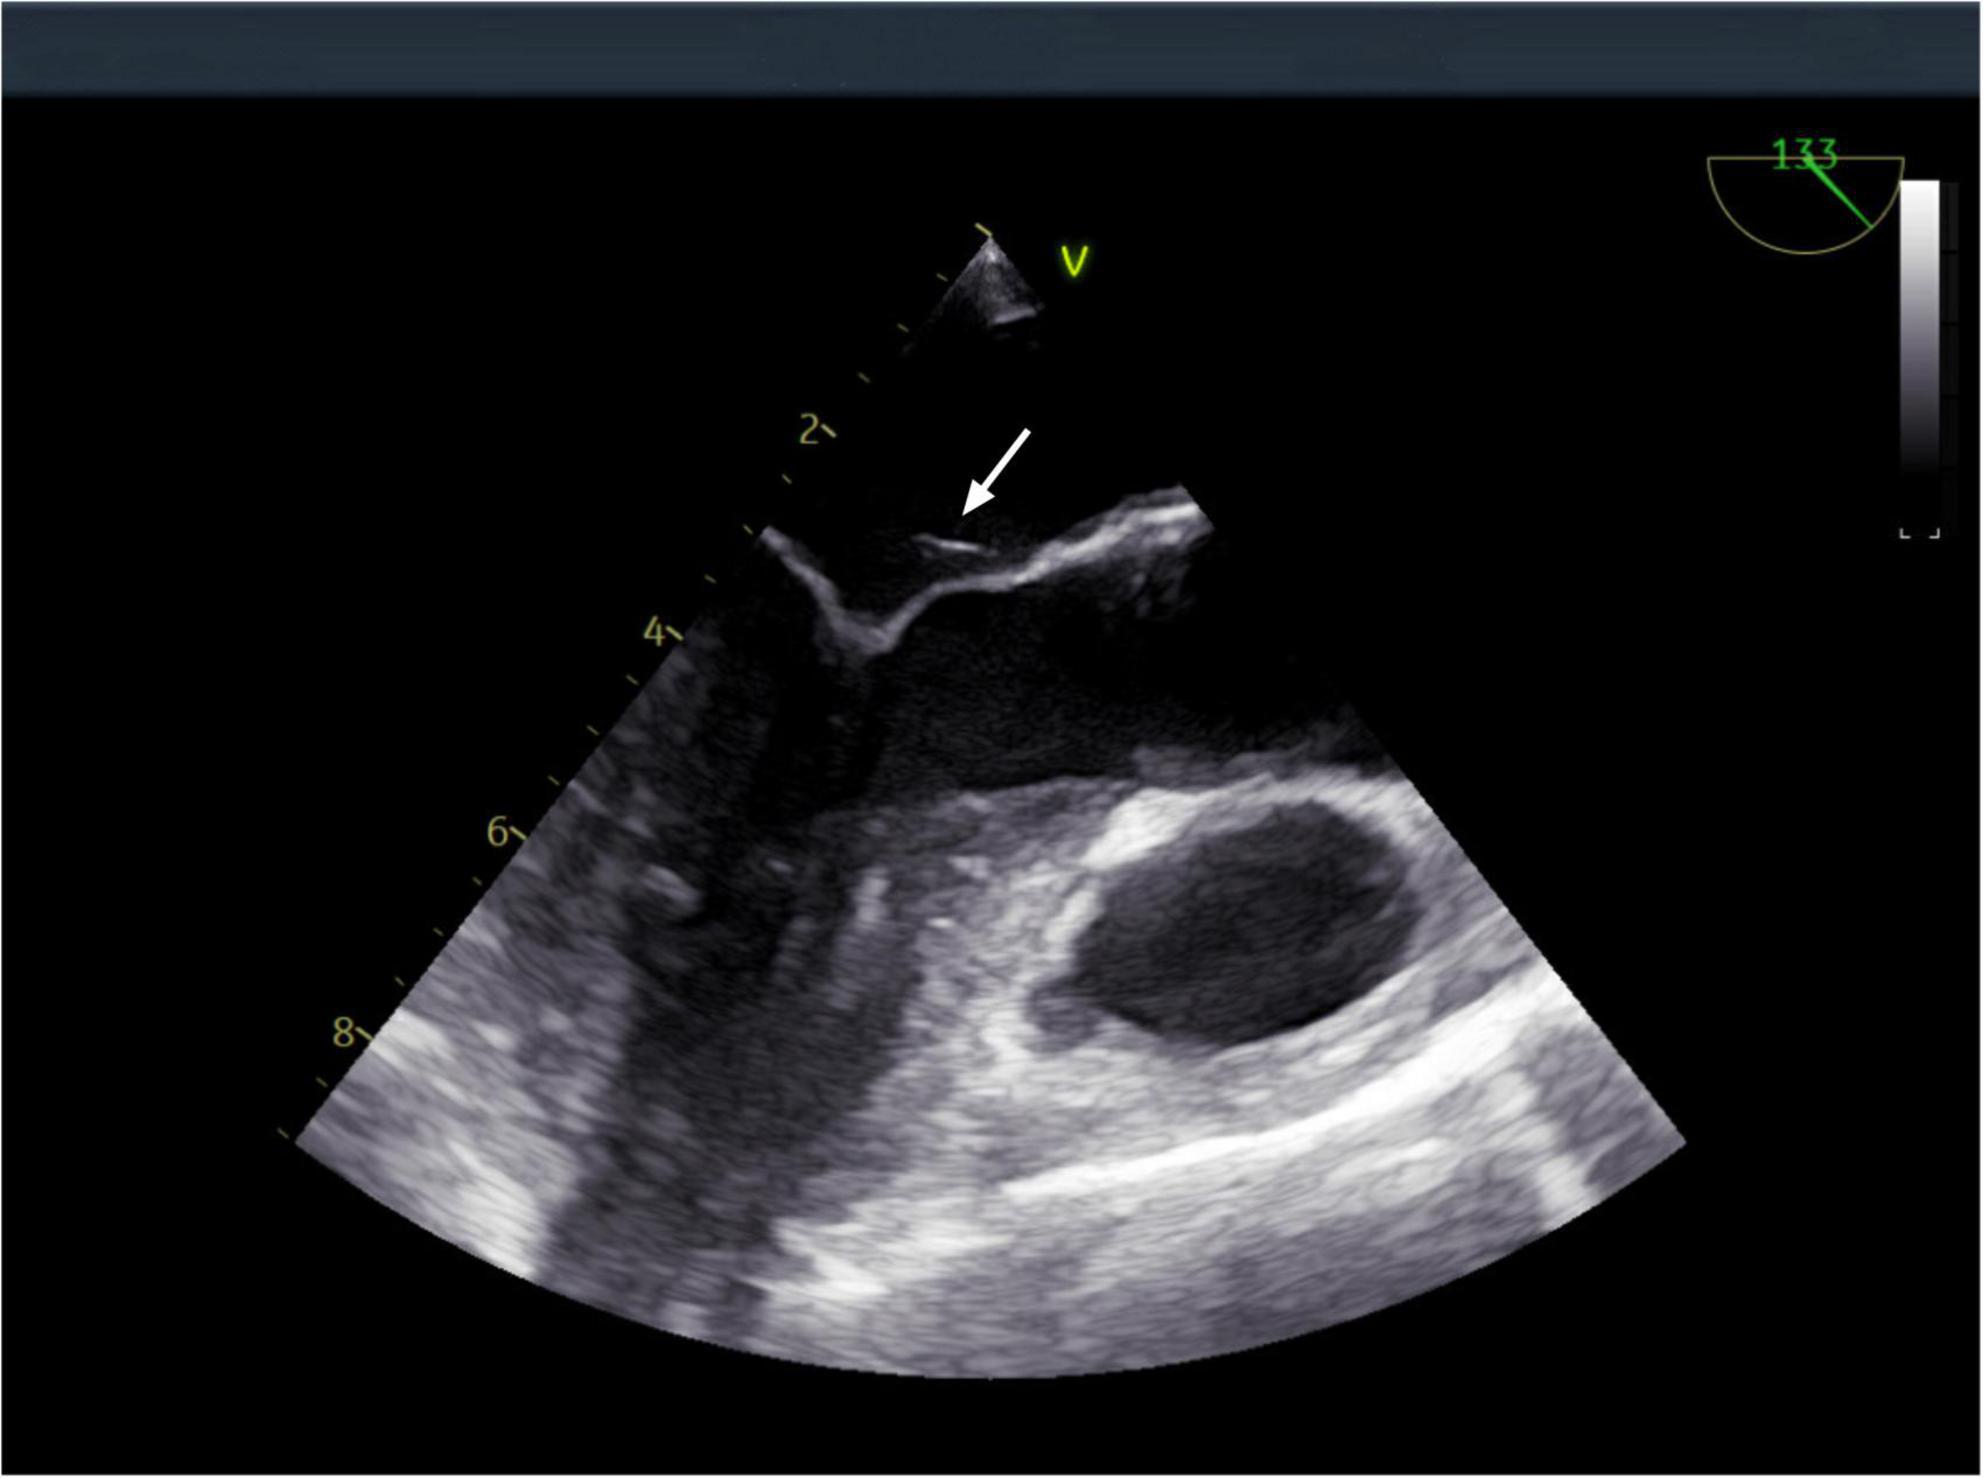

However, after completing 1 year of anti-tuberculosis therapy, the patient was re-admitted on March 15, 2024, due to recurrent low-grade fever. Repeat abdominal CT (Figure 1) showed progression of the hepatic lesion (now 5.1 × 2.0 × 3.6 cm) and persistent peritoneal thickening. Transesophageal echocardiography (TEE) revealed vegetations on the mitral valve (Figure 4), compatible with infective endocarditis.

FIGURE 4

Transesophageal echocardiography: a vegetation on the mitral valve was detected. The arrow indicates the location of the mitral valve vegetation.

During the patients second hospitalization, TEE demonstrated a mitral valve vegetation. In combination with metagenomic next-generation sequencing (mNGS) results, the diagnosis was suspected to be Q fever endocarditis. Q fever endocarditis is often associated with pre-existing valvular heart disease, immunosuppression, or pregnancy (22–24). Currently, doxycycline is the first-line treatment for Q fever (6),but in cases complicated by infective endocarditis, adjunctive hydroxychloroquine is recommended (25). Given this patient’s hypertensive retinopathy, doxycycline monotherapy was chosen, and the patient has been monitored for 14 months without recurrence.